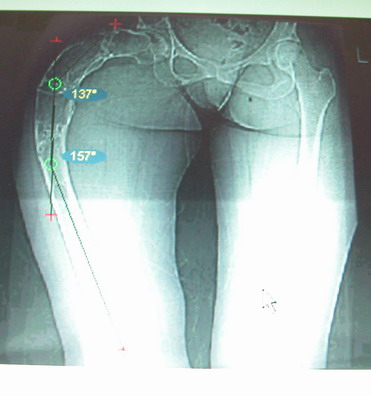

Женщина 28 лет, Больна с 12 летнего возраста, Когда после адекватной травмы получила перелом бедра. На рентгенограммах выявлено какое-то (рентгенограмм и документов нет) изменение бедренной кости, была оперирована, имеется гистологическое заключение - фиброзная дисплазия.дСформировалась деформация бедра. На сегодня - Укорочение 7см. Грубая деформация бедра по типу "пастушьей палки", последний патологический перелом в январе 2004г., консолидировавшийся при консервативном лечении. Имеются грубые изменения и в надвертлужном массиве.-- С уважением, Leonid

Возможна аппаратная коррекция оси с формированием клиновидного регенерата, которая решила бы и проблему укорочения (что, впрочем, нужно уточнить по схеме, сделанной по рентгенограмме с хорошим захватом смежных суставов - схемка по присланному снимку в приложении). По окончании коррекции - блокируемый стержень, который и сократит время пребывания в аппарате, и вообще возврата к нормальной жизни, а также будет мерой профилактики патологических переломов.

Собственно сустав не беспокоит, объем движений полный. По скиаграммам получается, что достаточно одной остеотомии на вершине деформации, чтобы восстановить длину и вывести коленный сустав в нужное положение.

Т.к. укорочение 7 см, то начинать будем с соеотомии и коррекции аппаратом. Спасибо